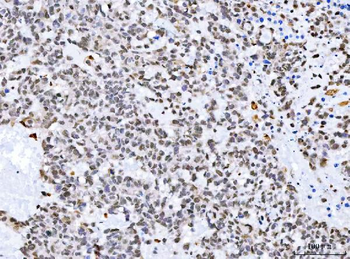

RARB Rabbit Polyclonal Antibody [orb11327]

FC, ICC, IF, IHC-Fr, IHC-P, WB

Bovine, Canine, Gallus, Porcine, Rat

Human, Mouse

Rabbit

Polyclonal

Unconjugated

50 μl, 100 μl, 200 μlTIG2 Rabbit Polyclonal Antibody [orb11481]